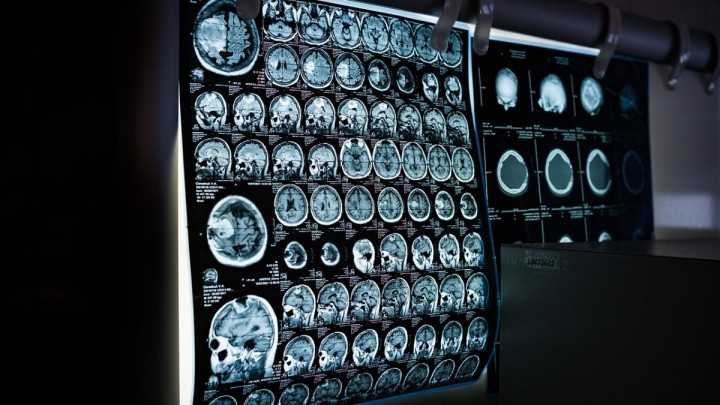

U Crnoj Gori godišnje 1.000 do 1.200 osoba doživi moždani udar